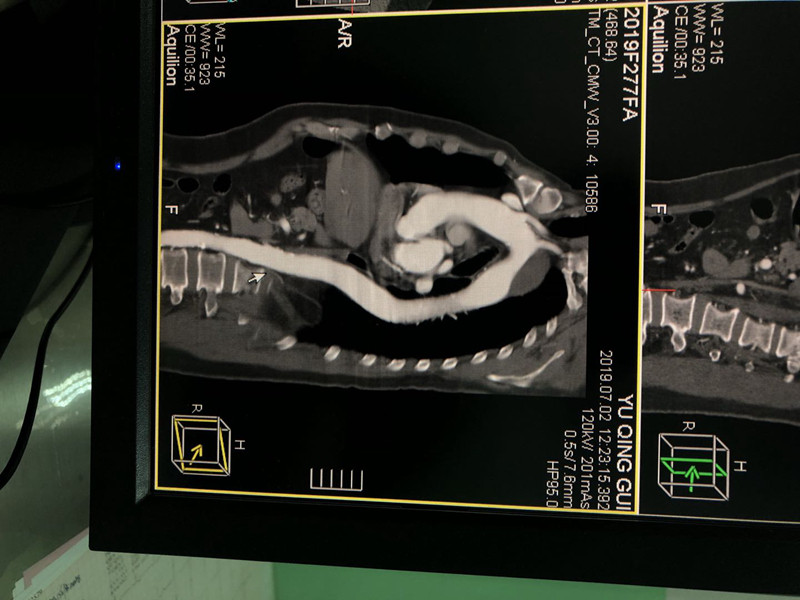

近日,我院介入医学科收治一名中年男性患者,主因“右侧肢体偏瘫”入院,急查发现患者脑出血,并发主动脉壁内血肿形成,给予锥颅脑内血肿引流后成功行主动脉腔内隔绝术,术后患者病情已趋于平稳,恢复良好。

该手术是我院、也是本地区首例主动脉壁内血肿腔内隔绝术,标志着我院的医疗技术水平上了一个新台阶,为我院以后开展急性动脉夹层手术提供技术储备,造福我区乃至整个白银市的患者。